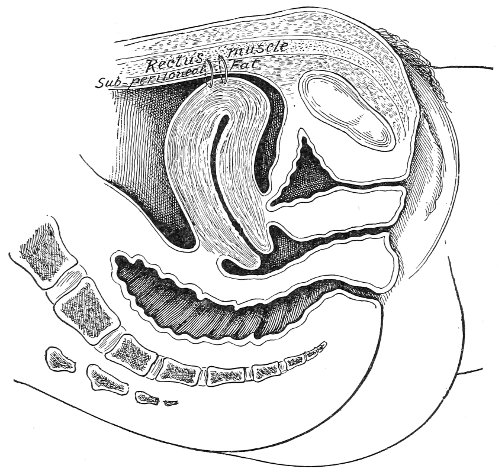

In making the bimanual examination the structures 25 should be palpated methodically in order. The vaginal finger notes the condition of the cervix uteri. If the fundus be in the normal position, the uterus can then be taken between the abdominal hand (upon the fundus) and the vaginal finger (upon the cervix) (Fig. 3). The shape, size, mobility, and consistency are noted. The vaginal finger is then passed anteriorly and laterally toward either uterine cornu, while the abdominal fingers pass over to the posterior aspect of the same cornu. The ovarian ligament and the proximal end of the Fallopian tube may thus be felt. Passing farther outward, the whole of the tube and the ovary may be examined. The same procedure is then applied to the opposite side.

Fig. 3.—Bimanual examination; median sagittal section of the pelvis.

The condition of the ureters may be determined by placing the vaginal finger in either lateral vaginal fornix and drawing it outward and forward, when these structures will pass over the end of the finger. When the 26 ureters are indurated by inflammation they can be plainly felt.